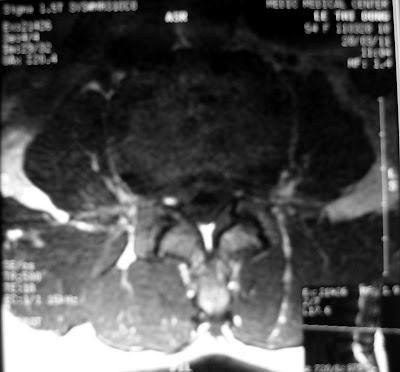

A 50 year- old male, 2M of LBP and L5, S1 left leg pain. His cafl is atroply, (35/31).,LATR 2/4. SLT 40. MRI show DH L4-5 with free disk fregment move down at the L5-S1 level. I did fenestration at L4-5 first, after taking out the L4-5 free disk fragment ,Left L5 nerve have swelled, so it have been narrow. I have been not sure that there was more free disk below susch as on MRI, so I did hemilaminectomy, athough I didnt see any thing more ,it make the L5 nerve more comfortable. Infact, the last axial picture show that the left nerv was swelled. we dont to do hemilaminectomy, I am sorry about it.